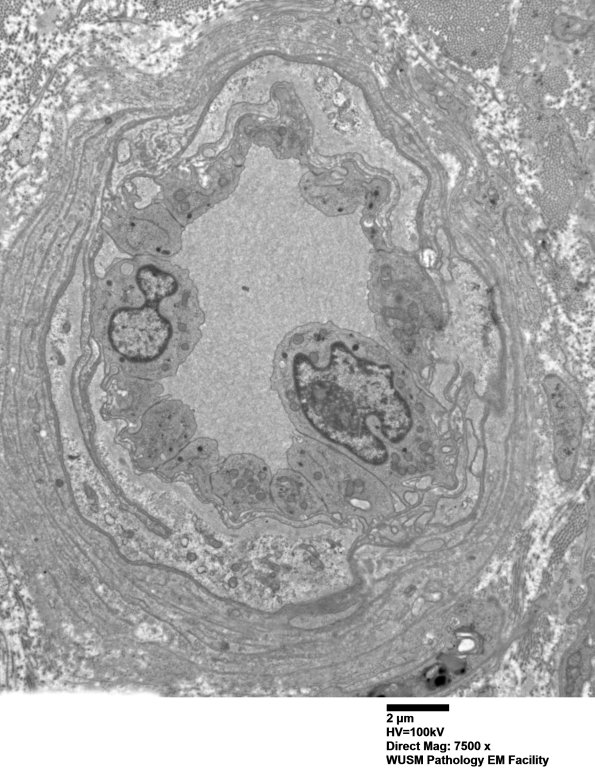

In this case the expanded wall is composed largely of basal membranes. (electron micrographs) ---- Interpretation: Humoral immune microvasculopathic neuropathy (HIEM) with C5b-9 deposition on endoneurial capillaries in some fascicles and moderate loss of large and small myelinated axons, variable between and within fascicles.